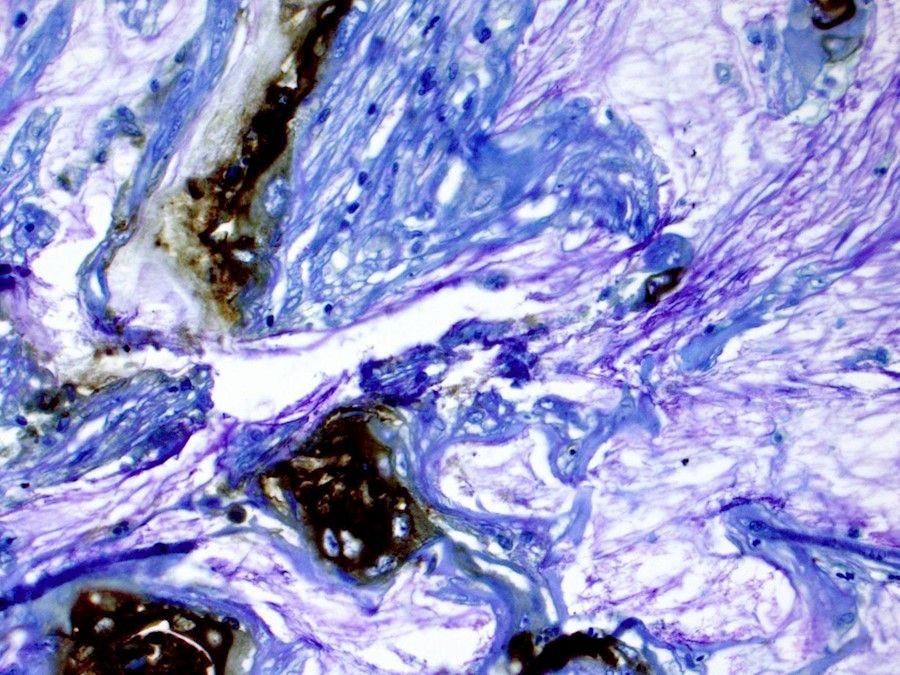

Las células cancerosas del páncreas parecen prosperar gracias a esta síntesis hiperactiva de colesterol. El equipo cree que esto es probablemente porque están aprovechando otras moléculas generadas por la misma vía. Son capaces de mantener la vía en funcionamiento y mantener su suministro gracias a una enzima llamada O-actiltransferasa 1 (SOAT1) del esterol, que convierte el colesterol libre en su forma almacenada y que las células cancerosas del páncreas tienen en abundancia.

Cuando los investigadores eliminaron la enzima SOAT1 mediante manipulación genética, evitando que las células convirtieran y almacenaran su colesterol, las células cancerosas dejaron de proliferar. En los experimentos con animales, la eliminación de la enzima detuvo el crecimiento del tumor.